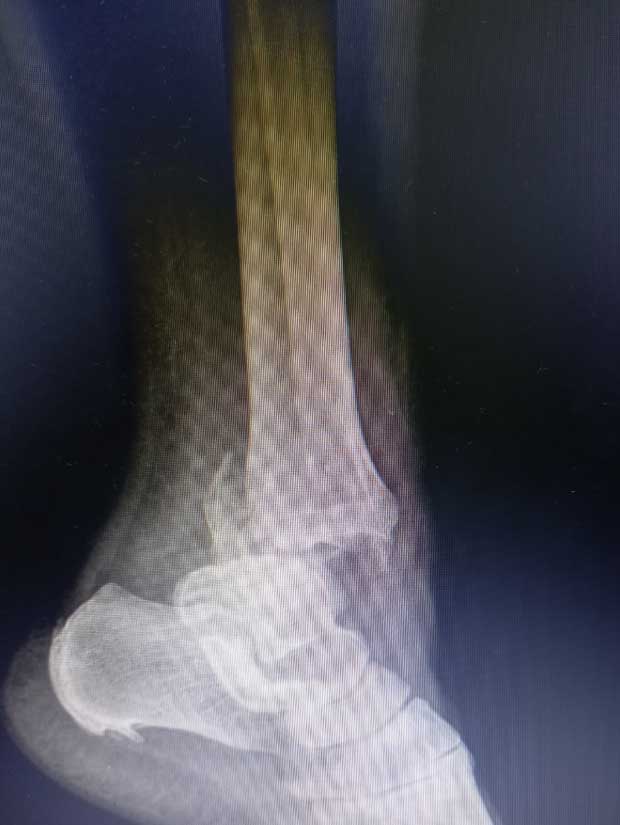

Caso No. 10 - Luxofractura de tobillo

Preoperación

Diagnóstico: Luxofractura de tobillo

Tratamiento: Cirugía: reducción abierta y fijación interna